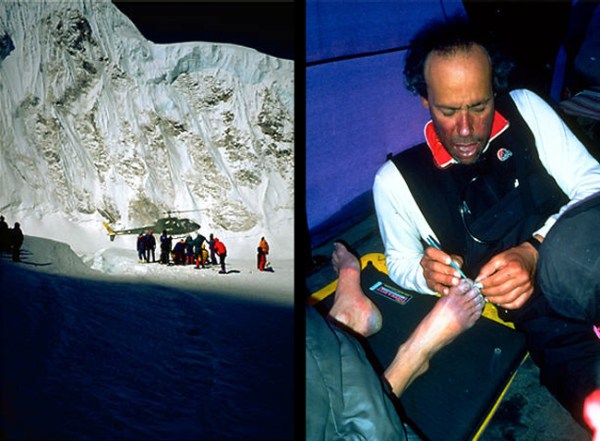

Detalle del rescate con helicóptero y del Doctor Ken practicando una de las curas. Fuente

Detalle del rescate con helicóptero y del Doctor Ken practicando una de las curas. Fuente

Con una camilla de sogas sus compañeros consiguieron evacuarlo al campo base, a 6.500 metros. Un helicóptero lo trasladaría, desde allí a un hospital en lo que se considera el rescate a mayor altura que ha hecho nunca una aeronave de esas características. Beck Weathers pasó hasta 10 veces por el quirófano durante su larguísima convalecencia. Le amputaron el brazo derecho a la altura del codo y los dedos de la mano izquierda y de los pies. También le reconstruyeron la nariz con trozos de piel de las piernas. Nunca más volvió a la montaña.